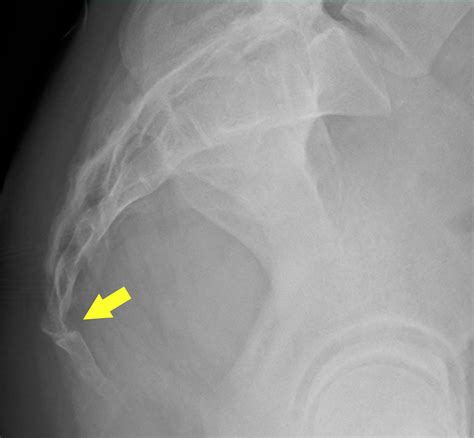

Diagnosing subluxation typically involves a combination of physical examination and imaging tests. A healthcare provider will perform a thorough evaluation to assess the spine's alignment and function. This may include:

• Imaging Tests: X-rays, MRI, or CT scans may be used to visualize the spine and identify any misalignments or abnormalities.